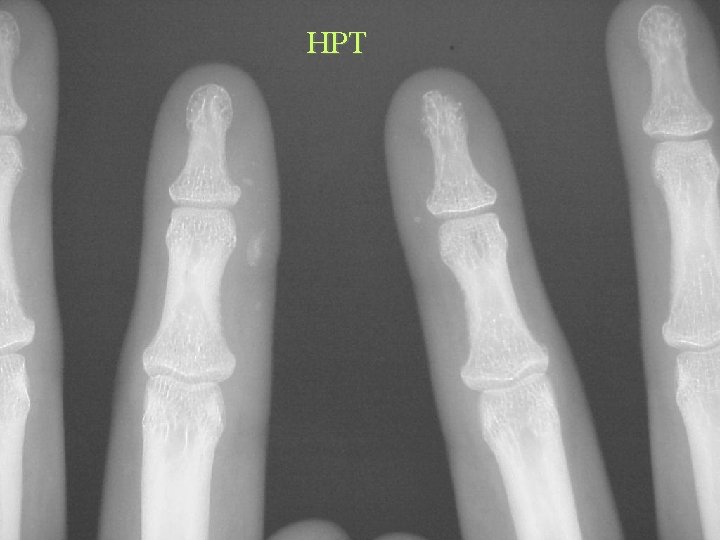

Soft Tissue Calcification By Cause Metastatic Calcification • Hyperparathyroidism • • • Hypoparathyroidism Renal Osteodystrophy Hypervitaminosis D Milk Alkali Sarcoidosis Massive bone destruction – Mets. , Myeloma, Leukaemia

HPT

Calcification By site Periarticular • Hyperparathyroidism • • Renal osteodystrophy Milk alkali syndrome Hypervitaminosis D Collagen vascular disease • Exclude intraarticular